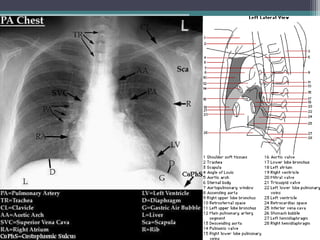

โ€ข PA and lateral chest films are the first step in

distinguishing from which mediastinal compartment

the mass is arising from.